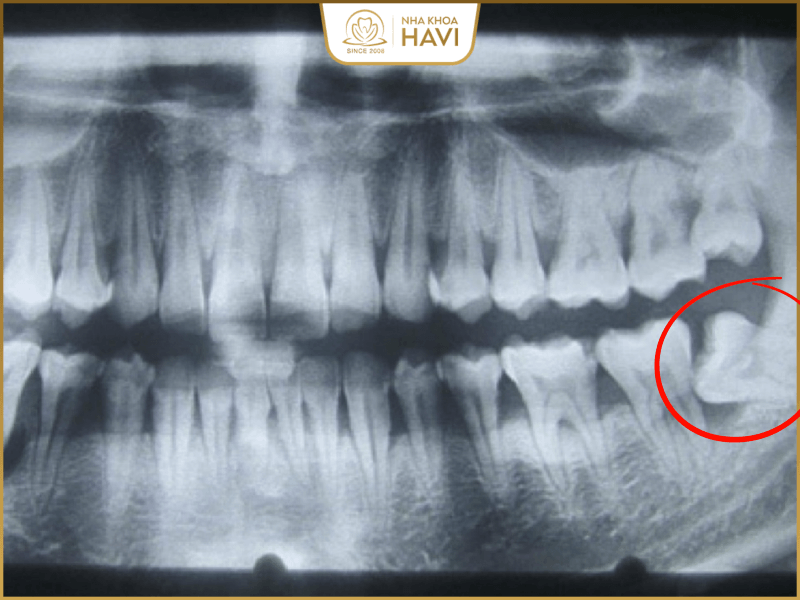

Giá nhổ răng khôn mọc ngầm

Tình trạng răng khôn mọc ngầm là tình trạng phức tạp nhất trong các trường hợp. Để có thể nhổ răng khôn mọc ngầm đòi hỏi người nhổ cần có kinh nghiệm và kỹ năng nhất định kết hợp với hệ thống máy móc hiện đại. Để nhổ nhanh chóng các bác sĩ cần xác định và rạch mổ đúng chỗ răng khôn đó để lấy ra nên rất khó. Mức giá nhổ răng khôn mọc ngầm sẽ đắt hơn so với những tình trạng khác. Bạn có thể tham khảo giá như sau:

- Răng khôn mọc ngầm ở mức độ 1 sẽ có mức giá nhổ răng là 3.000.000 đồng 1 răng.

- Chi phí nhổ răng khôn mọc ngầm mức độ 2 sẽ khoảng 5.000.000 đồng